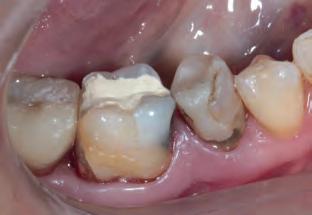

Fig. 2a: Patient was concerned about the discoloration on the two upper central incisors.

Fig. 2b: Old restorations were removed, and the surface was air-abraded with 50-micron aluminum oxide.

Fig. 2c: Freehand technique used to close the diastema.

Fig. 2d: The final result is at the one-year recall.